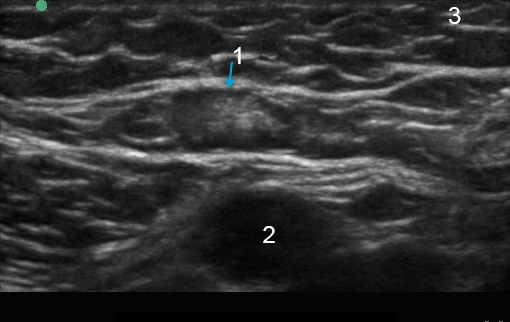

腋窩乳腺組織リンパ節像

リンパ節

動脈

乳房組織